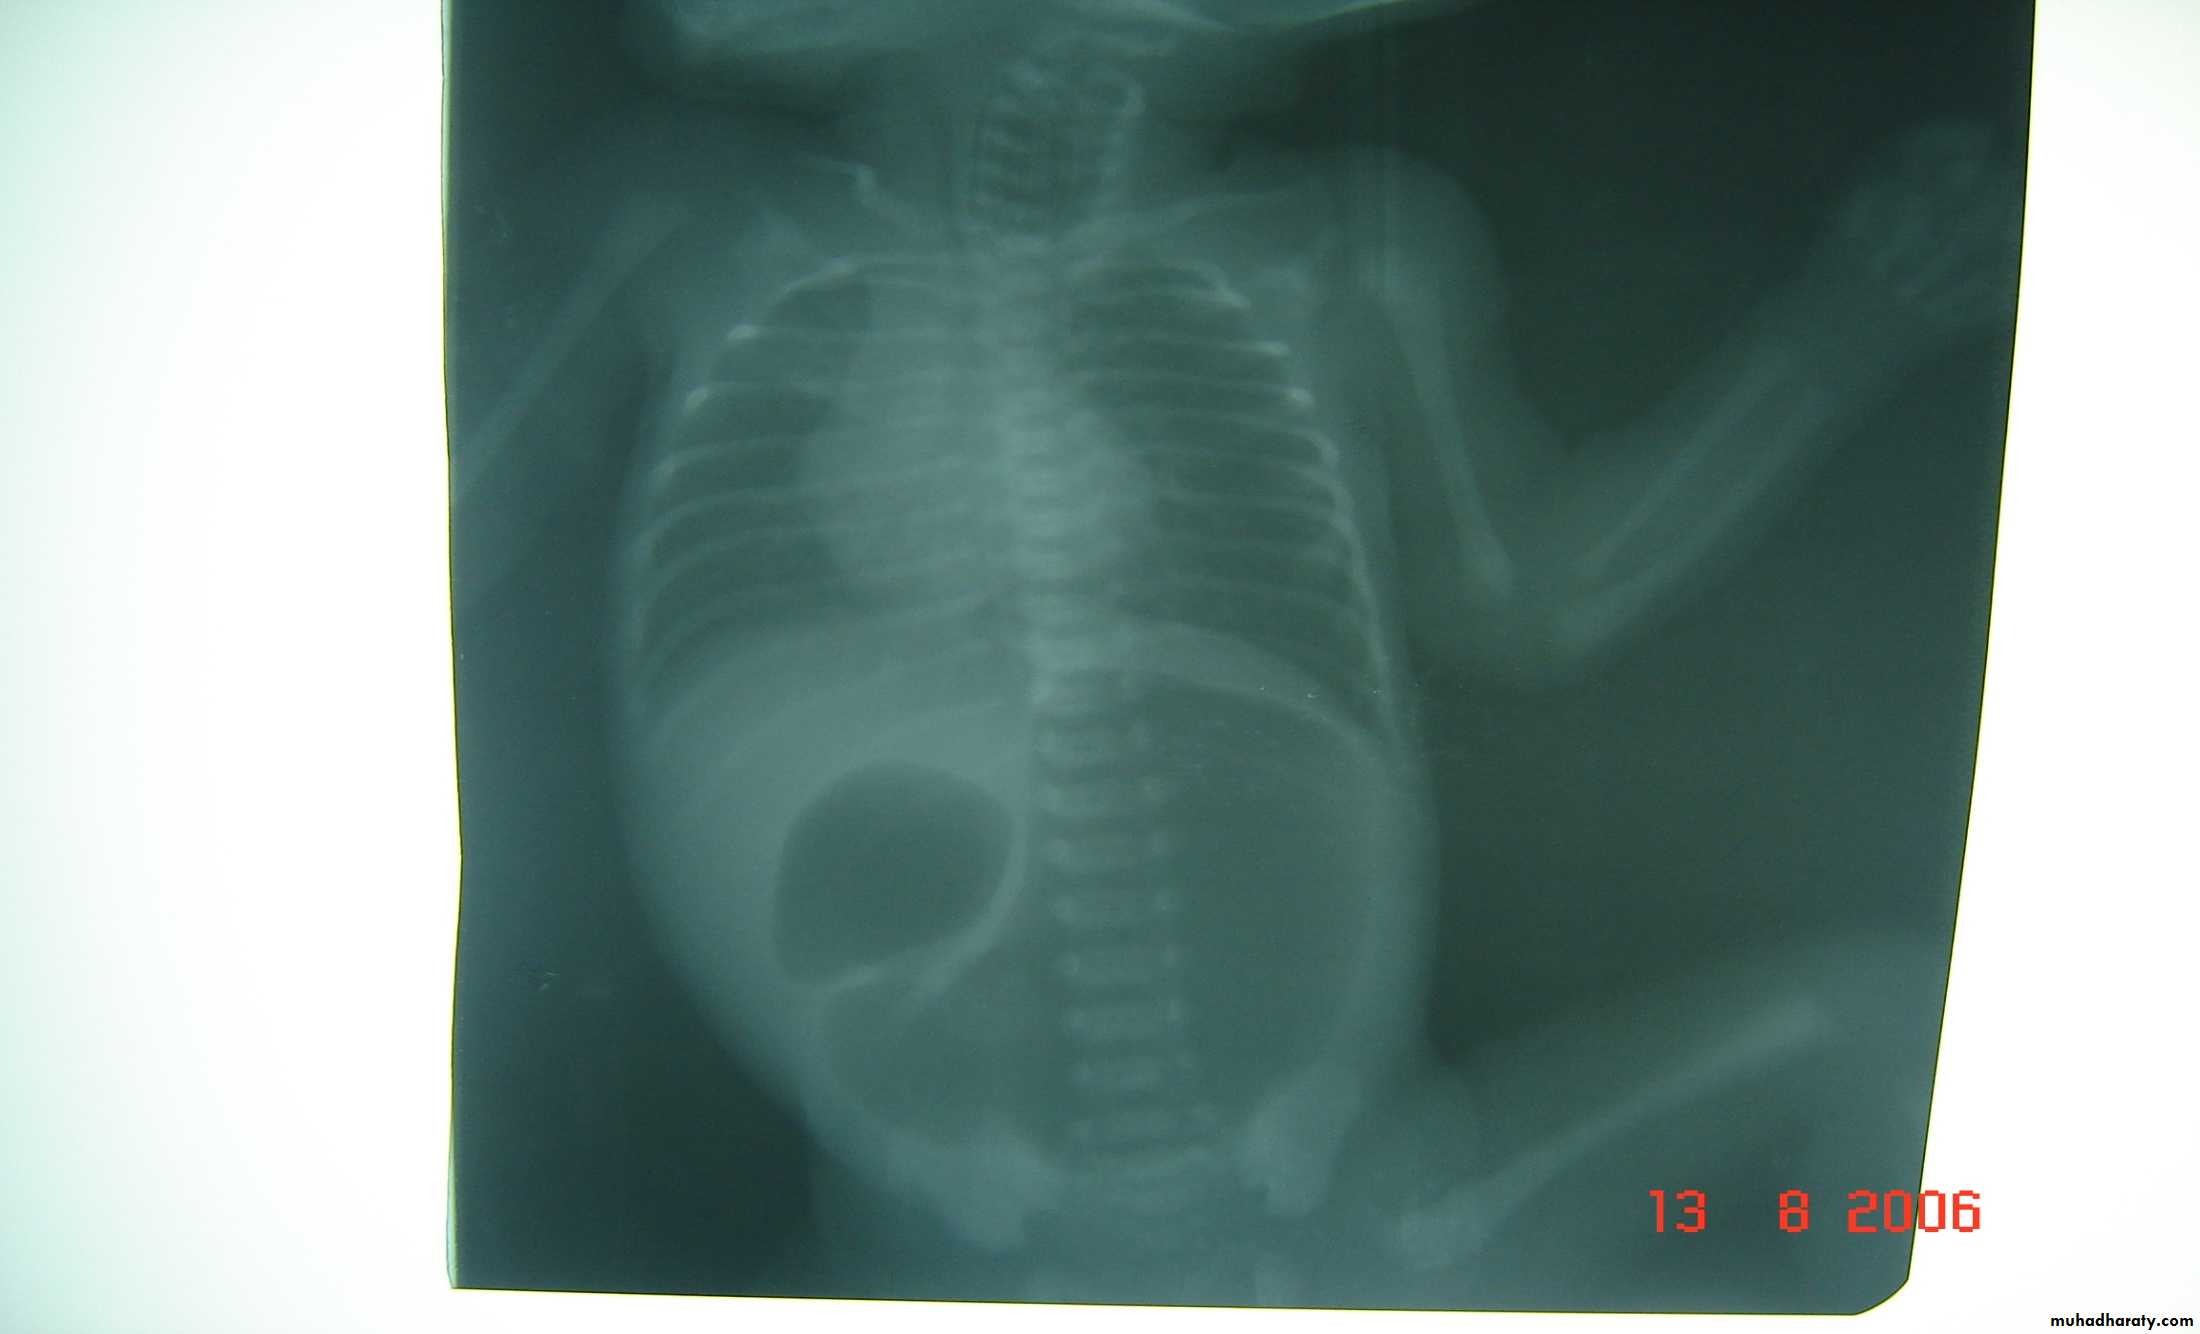

Defect=sac

Diaphragmatic eventration

plication